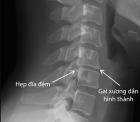

Gai cột sống là loại bệnh thoái hóa cột sống mà trong đó xuất hiện các phần xương mọc ra phía ngoài và hai bên của cột sống gọi là gai xương

Gai cột sống có thể xuất hiện ở nhiều vị trí trên xương sống của cơ thể nhưng thông thường hay gặp gai cột sống cổ và gai cột sống lưng

Hình ảnh: Gai cột sống